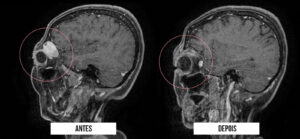

O Hospital Metropolitano Dom José Maria Pires – unidade pertencente à rede de saúde do Governo da Paraíba e gerenciado pela Fundação Paraibana de Gestão em Saúde (PB Saúde) – realizou, por meio da equipe de neurocirurgiões, a remoção de um tumor orbitário (região da órbita ocular, que se trata da cavidade anterior do crânio), em uma paciente de 55 anos, do município de Sousa. No procedimento exitoso, foi utilizada pela primeira vez a técnica endoscópica transorbitária, minimamente invasiva, que evita a abertura do crânio, e possibilita uma recuperação mais rápida ao paciente.

De acordo com o neurocirurgião responsável pelo procedimento, Breno Câmara, a técnica inovadora substitui a maneira convencional de retirada deste tipo de tumor, que é através de uma craniotomia, procedimento incisivo no couro cabeludo que pode trazer problemas funcionais e estéticos. “Utilizando o endoscópio de base de crânio, realizamos uma pequena incisão de menos de 3 centímetros na pálpebra superior da paciente o que possibilitou a visualização do campo cirúrgico através do endoscópio, e desse modo fizemos toda a remoção, com a garantia de trauma cirúrgico mínimo e com possibilidade de alta hospitalar em 48h”, destacou o especialista em tumores de base de crânio.

O resultado clínico de Maria Aparecida foi excelente, segundo o neurocirurgião Eduardo Guedes. “A paciente teve sua lesão completamente ressecada, encontra-se sem sequelas e a incisão apresenta estética excelente. Vale destacar que, além dos benefícios para a paciente, a técnica reduz custos hospitalares, pois não houve a necessidade de qualquer material OPME (aquisição específica para uma cirurgia), e os custos relacionados à internação também reduz, pois o período é bem mais curto”, frisou.